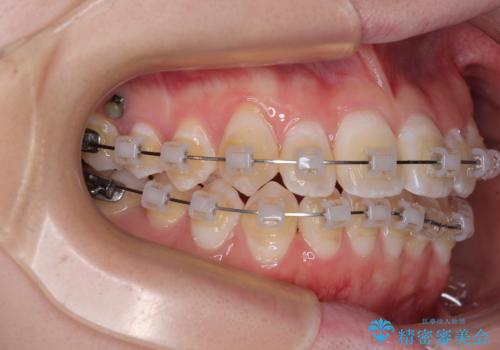

- クリアブラケット

目立ちにくさと費用のバランスを考慮し、プラスチックブラケット+メタルワイヤーを採用。日常生活でも装置の存在感を気にせずお過ごしいただけます。

患者様の協力もあり、およそ1年間で治療を完了。スムーズな歯の移動を実現しました。